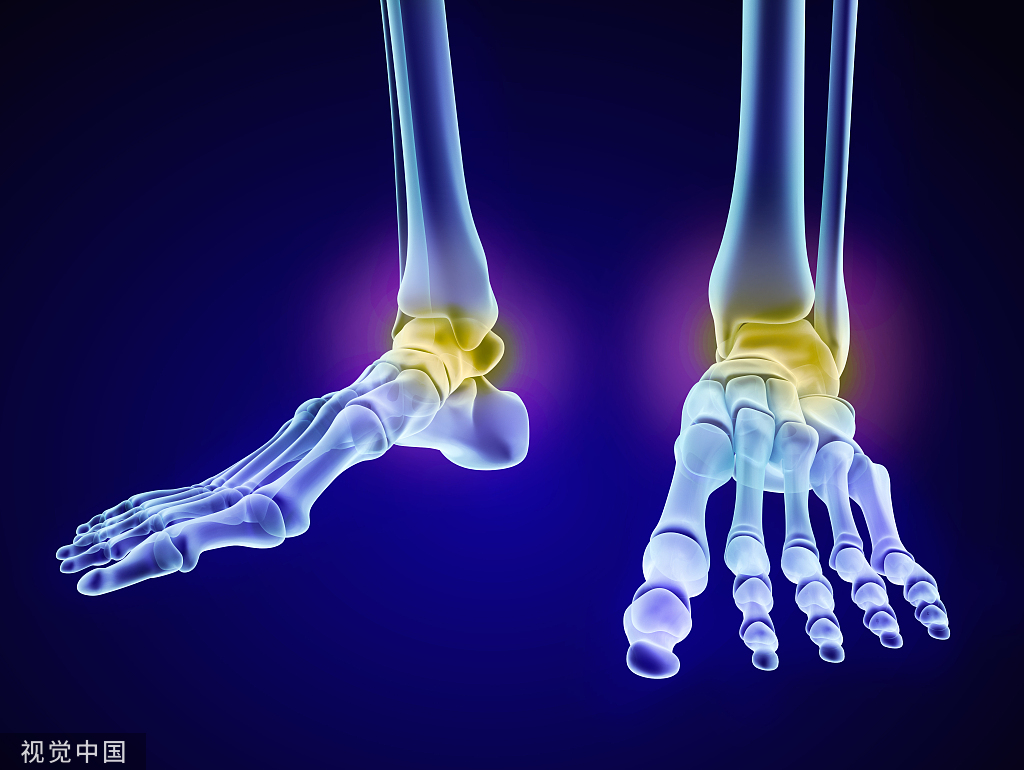

桡骨远端骨折属于常见的上肢骨折疾病,随着社会发展,工作及生活节奏不断加快,车祸和高处坠落等也会使得桡骨远端严重骨折的发生率明显上升。